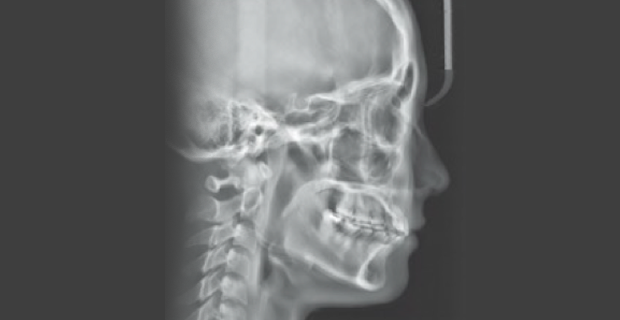

• Cephalometric X-ray 촬영

2~3초의 짧은 시간 안에

얼굴의 측면 엑스레이 촬영이 가능합니다.